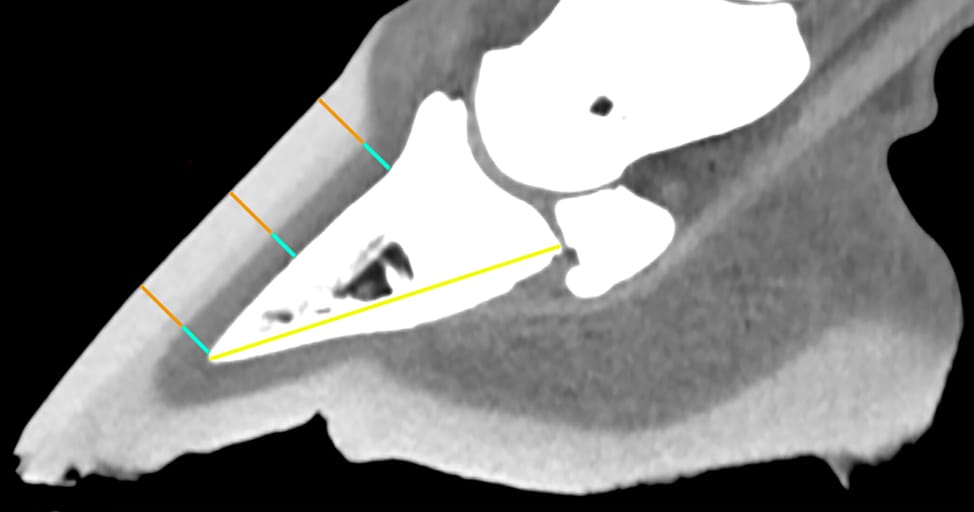

Midsagittal computed tomographic reconstruction of a foot, using soft tissue algorithm, demonstrating measurements of the deep layer (blue lines), superficial layer (orange lines), and total hoof wall (blue lines plus orange lines) at three measurement points. The palmar length of the distal phalanx is measured from the tip of the distal phalanx to its articulation with the distal sesamoid bone (yellow line).